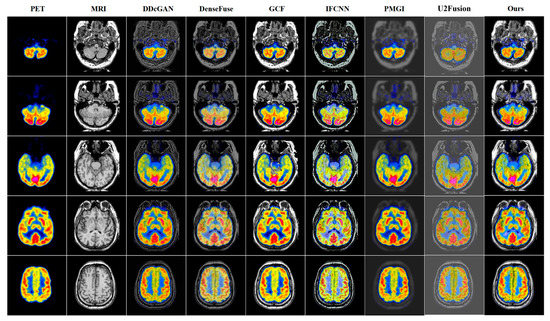

PET-MRI | DDcGAN | DenseFuse | GCF | IFCNN | PMGI | U2Fusion | Ours |

---|---|---|---|---|---|---|---|

AG↑ | 6.0128 | 4.9272 | 7.0089 | 6.9044 | 2.7804 | 3.8598 | 8.3813 |

EI↑ | 60.3775 | 51.1228 | 75.6065 | 73.8009 | 29.6103 | 40.6413 | 84.7561 |

Qabf↑ | 0.3655 | 0.2863 | 0.5848 | 0.5026 | 0.1736 | 0.1705 | 0.6456 |

Qcv↓ | 1577.441 | 947.514 | 718.393 | 412.393 | 3667.634 | 1861.1615 | 220.779 |